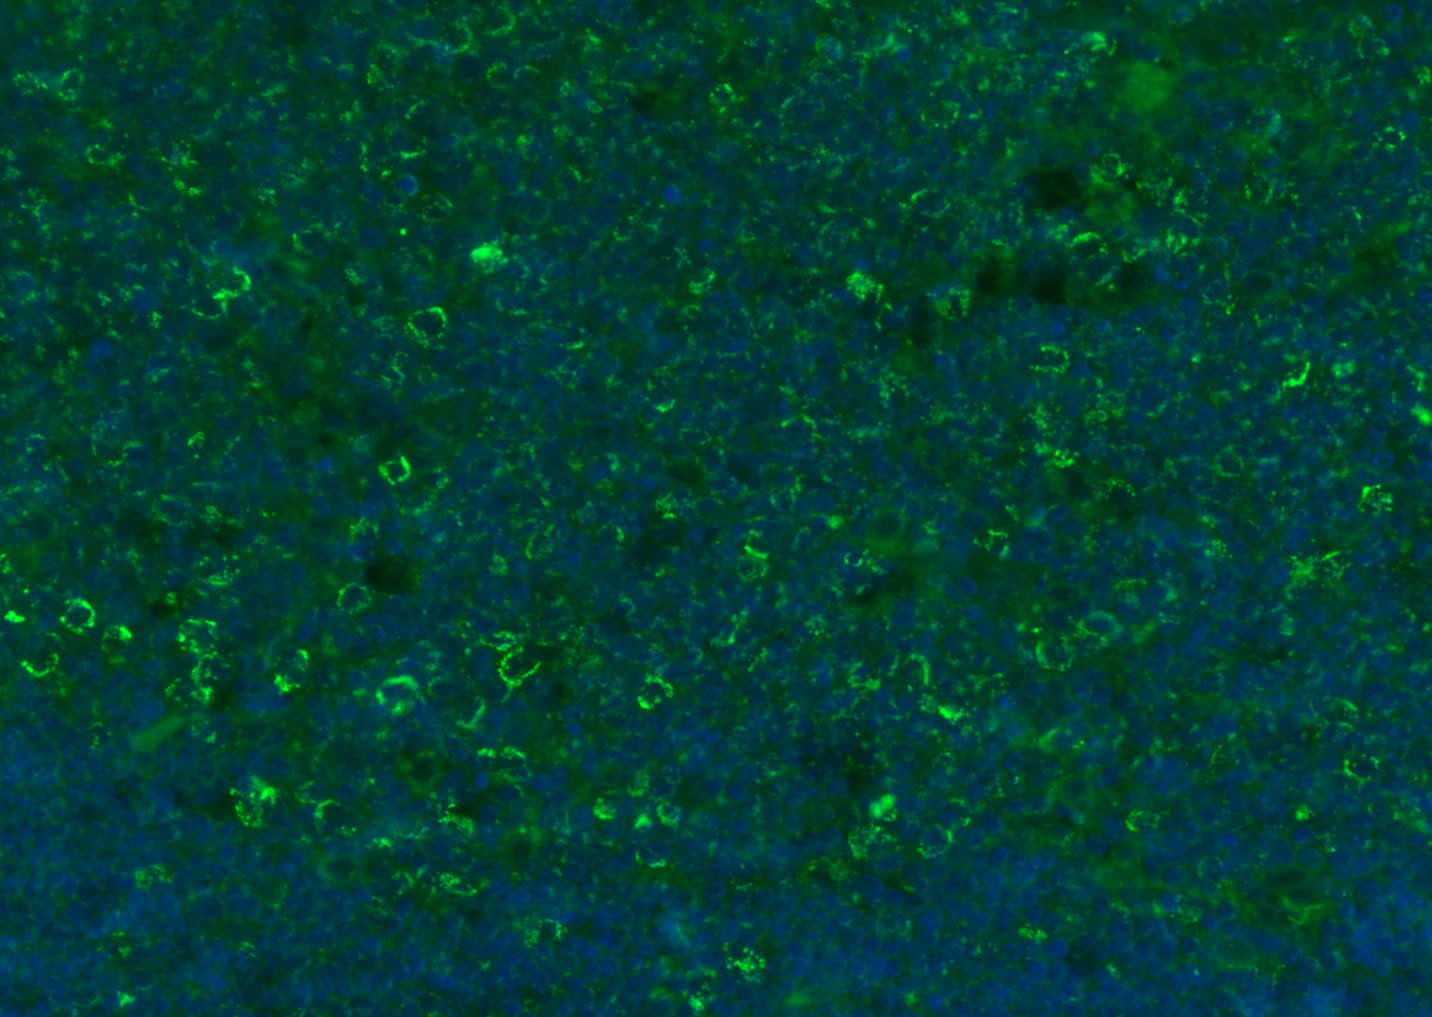

Paraformaldehyde-fixed, paraffin embedded (rat thymus); Antigen retrieval by boiling in sodium citrate buffer (pH6.0) for 15min; Blocking buffer (normal goat serum) at 37°C for 30min; Antibody incubation with (CD8B) Polyclonal Antibody, Unconjugated (bs-4914R) at 1:200 overnight at 4°C, followed by a conjugated Goat Anti-Rabbit IgG antibody (bs-0295G-FITC) for 90 minutes, and DAPI for nuclei staining.